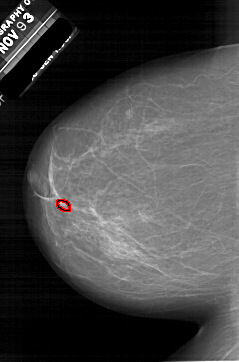

A_1952_1.LEFT_MLO

LEFT_MLO LINES 6391 PIXELS_PER_LINE 4291 BITS_PER_PIXEL 12 RESOLUTION 43.5 OVERLAY

FILE: A_1952_1.LEFT_MLO.OVERLAY

TOTAL_ABNORMALITIES 1

ABNORMALITY 1

LESION_TYPE CALCIFICATION TYPE PLEOMORPHIC DISTRIBUTION CLUSTERED

ASSESSMENT 4

SUBTLETY 2

PATHOLOGY BENIGN

TOTAL_OUTLINES 1

BOUNDARY